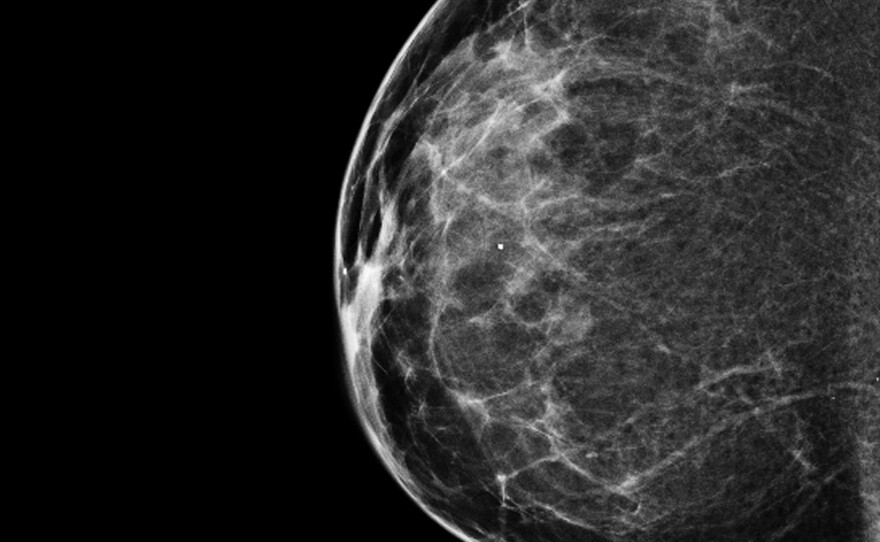

A 3-D mammogram reveals a normal breast.

Both types of tests use X-ray technology to create images of the breast. The 2-D digital mammograms that most women receive typically provide front and side images. For the 3-D test, the X-ray arcs across the breast, creating multiple images of breast tissue. The experience is the same for women, though, because both scans involve compressing the breast between two plates extending from the machine.